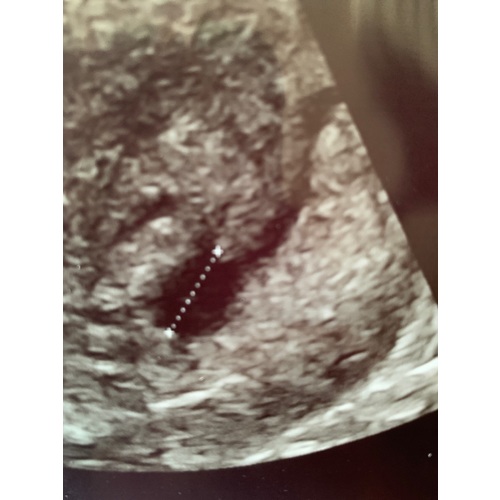

Vanmorgen een spoed echo gehad omdat ik wat bruine afscheiding had bij het afvegen. Moest vandaag komen voor een echo omdat ik eerder een MA heb gehad. Zou volgens berekeningen 5.5 moeten zijn, maar helaas nog een leeg vruchtzakje. Ik probeer positief te blijven en jullie positieve berichten te lezen om hoop te houden. Volgende week terug en hopen op ontwikkeling 🤞🏻🍀🐞

maar je heb wel een ringgg erin mischien is je baby toch iets kleiner ik had het ook kijk later kwam er een ringetje in wat jij heb op je echo fototje, 1 week later zag je me baby🥰

Ik dacht op deze 2e foto ook een ringetje te zien!! Zie jij het ook? Rechts onder? We houden hoop 🤞🏻🍀🙏🏼